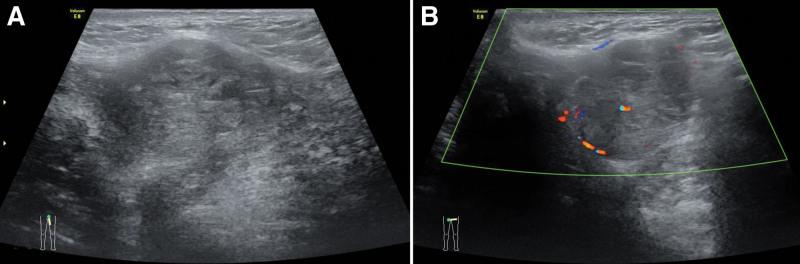

A 58-year-old female was referred to our hospital for further valuation of a mass occurring on the left side of her vulva. In the other hospital, the beginning of the period, local ultrasound showed a vulva mass, which was suspected to be a Bartholin's gland cyst. Mixed neoplasms were considered in some biopsies. When transferred to our hospital, virtuous tumors were considered by ultrasound and magnetic resonance imaging. Pathology initially considered benign hyperplastic active tumor or borderline tumor.

一名 58 岁女性因左侧外阴出现肿块而被转至我院进一步评估。在另一家医院,初诊时,局部超声显示外阴肿块,疑似巴氏腺囊肿。部分活检考虑为混合性肿瘤。转至我院时,超声和磁共振成像考虑为良性肿瘤。最初的病理检查考虑为良性增生性活性肿瘤或交界性肿瘤。